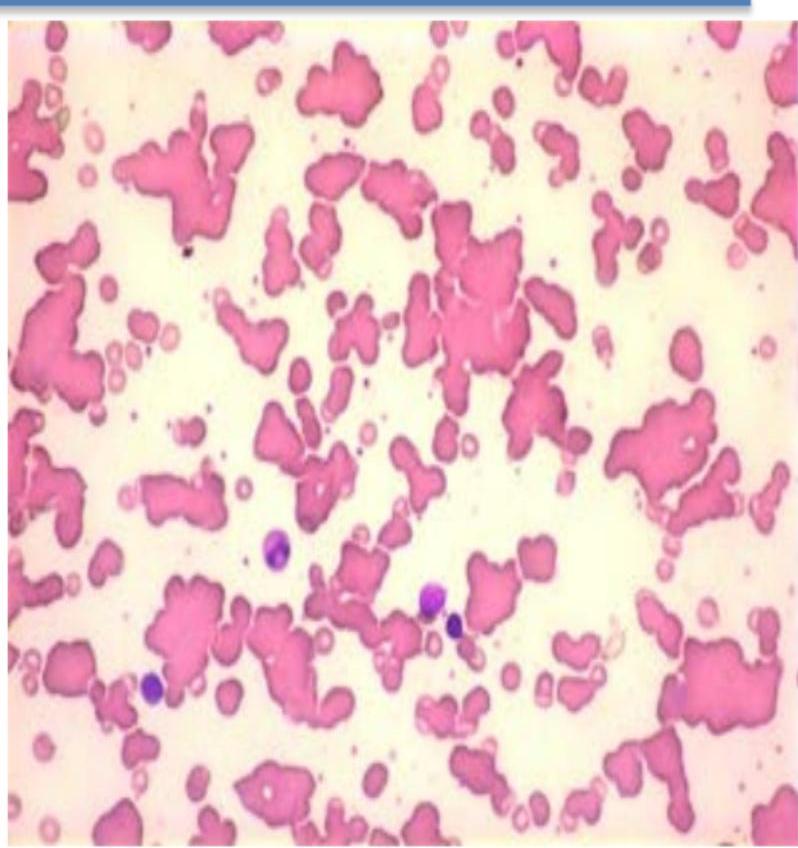

Peripheral blood picture

This is used now → blood injected in machine and machine does calculations → investigation needed to make a diagnosis is not used as much now → always needed in addition to automated cell counters.

A blood film examined by a haematologist or technician experienced in blood cell morphology is still an essential adjunct to the above, as definitive abnormalities of cells can be seen. → peripheral blood picture can diagnose

Normal Blood Smear - RBCs